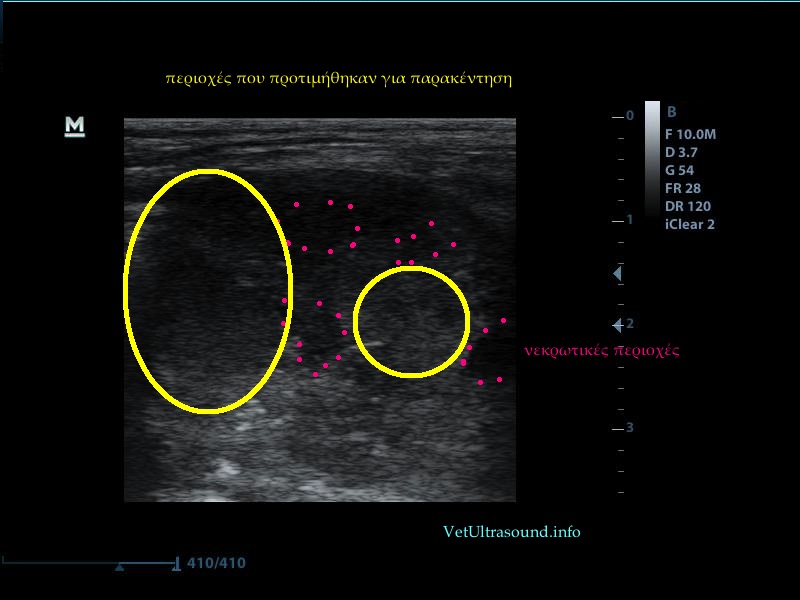

Στον υπέρηχο εμφανίζονταν αρκετές περιοχές υποηχογενείς, πιθανόν νεκρωτικές, ενώ αντίθετα στην περιφέρεια της μάζας η εικόνα του ιστού φαινόταν αρκετά πιο συμπαγής. Για να έχουμε καλό κυτταρολογικό υλικό προτιμήσαμε την περιφέρεια της αλλοίωσης ώστε να μην πάρουμε φλεγμονικά κύτταρα και κυτταρικά ράκη από τις νεκρωτικές περιοχές. Η αιμάτωση της μάζας ήταν μειωμένη, έτσι ο κίνδυνος τρώσης κάποιου αγγείου ήταν μειωμένος. Σε περίπτωση που η αλλοίωση βρίσκεται πιο βαθειά ή έχει έντονη αιμάτωση, η μέθοδος εκλογής για βιοψία ή FNA είναι η αξονική τομογραφία.